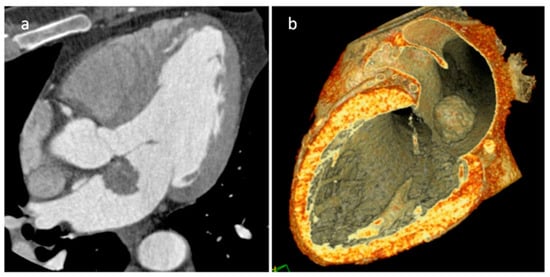

| LHIS | Late adulthood. Obesity | IAS | Usually, asymptomatic. Atrial arrhythmias | mass like deposition of brown fat in the IAS which spares the fossa ovalis | Homogeneous hyperechoic dumbbell appearance of atrial septum | mass with fat-attenuation which spares the fossa ovalis | Hyper T1w and T2w, no LGE, hypo on STIR and other fat-suppression sequences |

| Myxoma | Adulthood. Carney complex. | LA | Usually, asymptomatic. Rarely, intracardiac obstruction, embolic events and constitutional symptoms | Mobile mass arising from the IAS | Globular or spherical, with a friable surface and heterogeneous internal echogenicity | Heterogeneous, low attenuation, may be calcified | Isointense T1w, High T2w, heterogeneous LGE |